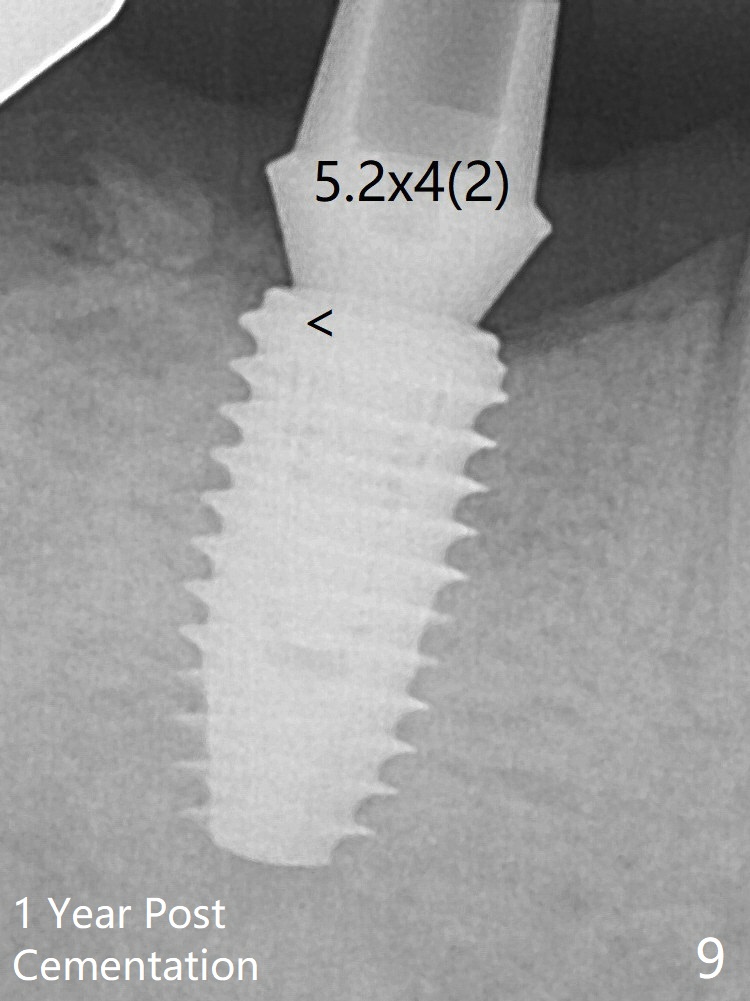

To reduce heat-induced bone necrosis at #19, osteotomy is conducted slowly with copious irrigation with cold saline. Bone density is felt while a 5x10 mm implant is being placed after using cortical tap to the 2nd line of the implant driver. The implant needs to be reverse torqued several times before reaching its final depth (Fig.1 (~50 Ncm)). Since the residual roots are superficially positioned, the immediate implant looks as a delayed one. Although the implant is placed mesial to the septum clinically, its position in X-ray seems to be normal. Because of severe wear and lack of vertical height, a 6.8x5 mm healing abutment is placed. Retention of bone graft placed in the distal socket (Fig.1 *) is maintained by spreading setting acrylic into the edentulous undercut areas. The bone graft placed in the distal socket appears to have been converted to the native bone 3.5 months and 4 months postop (Fig.4,6). There is no bone loss 5 months post cementation, although the abutment screw has been loose (Fig.7). The patient complains of food impaction nearly 1 year post cementation. The mesial and distal contacts of #30 crowns are light. When the abutment/crown is removed, there is implant well contamination (food debris). It appears that the previous abutment (5.7x4(2) mm, Fig.6,7) is incompletely seated. When a smaller abutment is placed and torqued at 30 Ncm, it is seated fully (Fig.9 (<: no gap)). New impression is taken. If there is food impaction distal to the new crown, the distal crestal bone should be removed with lab closure of the embrasure.